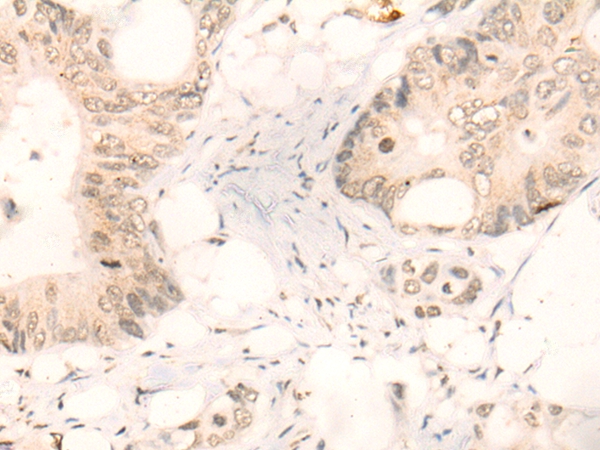

分类: 科研抗体货号: P43512别名: Collagen alpha-1(I) chain (Alpha-1 type I collagen)应用: IHC反应种属: Human,Mouse,Rat